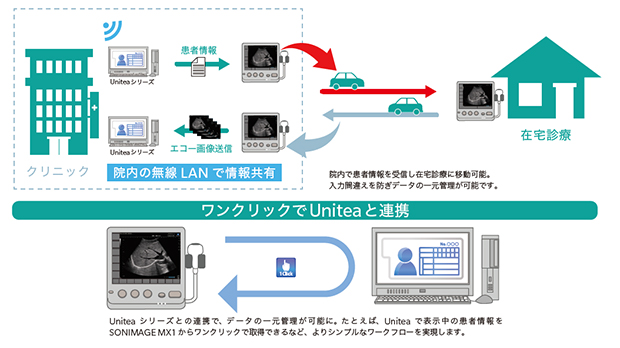

ワークフローの効率化 院内システムとの連携

・無線LANキット

・DICOMライセンス(Worklist,Storage)

・電子カルテ連携機能

・Unitea連携機能